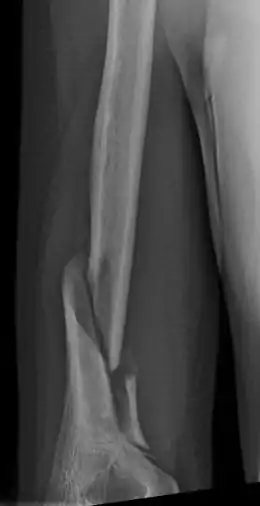

Holstein–Lewis fracture

| Holstein–Lewis fracture at 5 weeks post fracture | |

A Holstein–Lewis fracture is a fracture of the distal third of the humerus resulting in entrapment of the radial nerve.